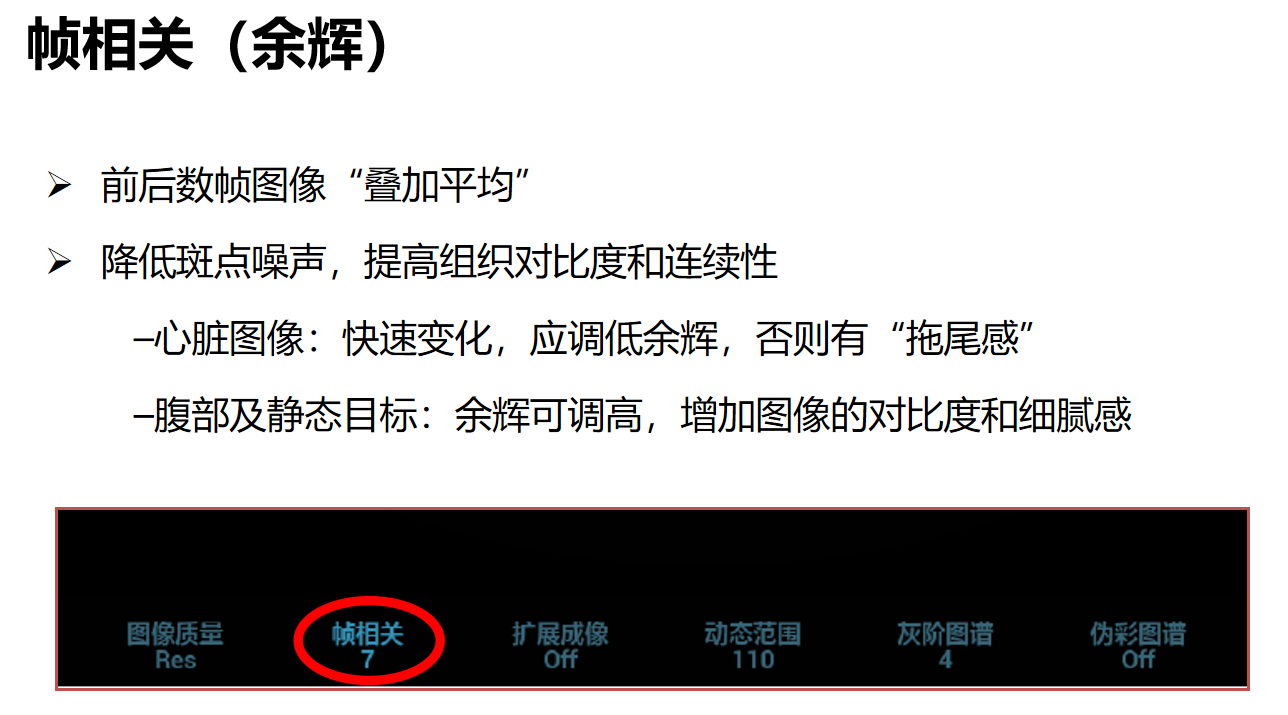

帧相关:帧相关在上彩色时叫余辉,帧相关是将相邻帧图像进行叠加平均,降低图像噪声,进行图像优化,使图像更细腻。

数值越大,优化越明显,但是有可能造成特异性信息的丢失。

做心脏时,因为心脏跳动较快,应适当降低帧相关,否则感觉图像跟不上,有种拖尾感;做腹部和浅表器官时,因为他们运动幅度较小,可以把帧相关适当调高,增加图像的对比度和细腻感。